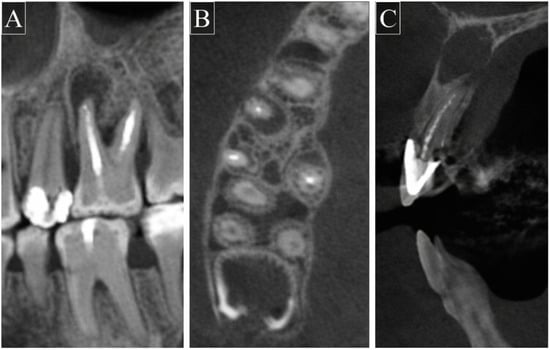

Each CBCT volume was assessed in the axial, sagittal, and coronal planes. A diagnosis of apical periodontitis was recorded only when a periapical radiolucency was visible in more than one imaging plane. Apical periodontitis was defined according to the criteria described by De Moor et al. [16] as a periapical radiolucency associated with the apical portion of the root exceeding twice the normal width of the periodontal ligament space. Representative CBCT images illustrating the diagnostic criteria are shown in Figure 2.

Figure 2.

Representative cone-beam computed tomography (CBCT) images demonstrating apical periodontitis in root canal-treated teeth. (A) Coronal view showing periapical radiolucency associated with the treated root of tooth #26. (B) Axial view illustrating periapical radiolucency at the root apex of tooth #16. (C) Sagittal view confirming the periapical radiolucency associated with tooth #11.